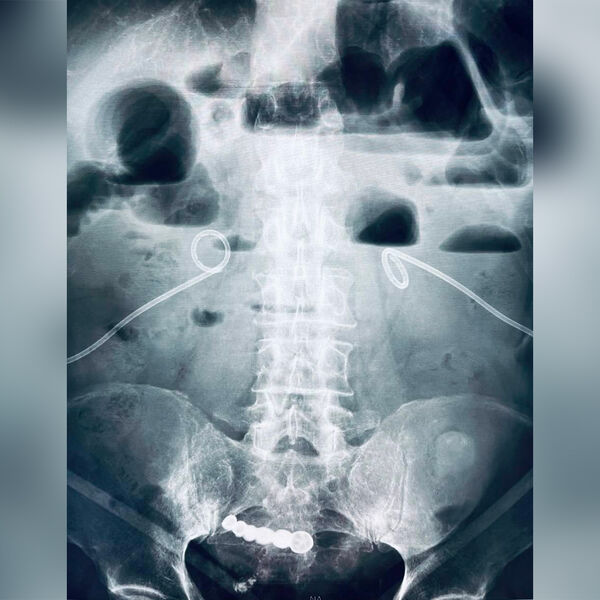

Пенсионер из Кемеровской области шесть лет прожил со вставной челюстью в кишечнике, мужчина случайно проглотил инородный предмет и не обращался к врачам. Об этом сообщил глава регионального Минздрава Дмитрий Беглов на странице во «ВКонтакте».

Пожилой мужчина обратился в городскую больницу Кемерова с жалобами на острою боль в области живота. В ходе обследования медики обнаружили в кишечнике пенсионера зубной протез, пациент рассказал врачам, что шесть лет назад случайно проглотил вставную челюсть.

Инородное тело не доставляло неудобств, и мужчина решил не обращаться к врачам. Вставную челюсть удалили малоинвазивным методом. Пенсионер выписан на амбулаторное лечение.